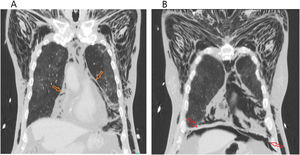

Worsening of severe respiratory failure with no significant response to medical therapy (antibiotic and corticosteroid) required escalation of care, transfer to intensive care unit and endotracheal intubation. Then, after 4 days, development of significant cervical subcutaneous emphysema (Fig. 1A) raised suspicion of potencial air trapping, with confirmation of sachular bronchiectasis, severe pneumomediastinum (Fig. 1B and Fig. 2A) and discrete pneumoperitoneum (Fig. 2B) in subsequent thoracic CT-scan. Notably present was also the characteristic COVID-19 pneumonia pattern – diffuse peripheric ground-glass opacity (Fig. 2B).

Thoracic CT scan (axial plane) revealing extensive subcutaneous cervical and thoracic emphysema (red arrows) with discernible muscular fibres dissection. Green arrow pointing to finding of predominant anterior pneumomediastinum. COVID pneumonia typical peripheral consolidation with ground-glass opacification (orange arrow).